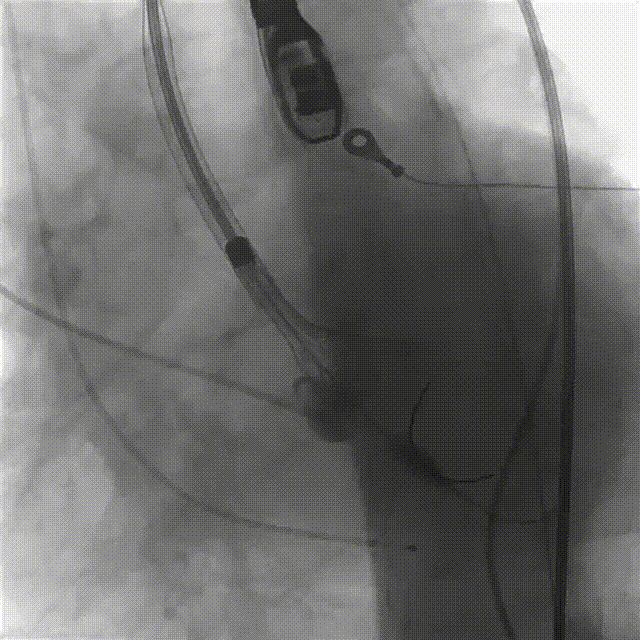

5.根据术前评估及球囊预扩情况,选择23mm沛嘉TaurusElite瓣膜进行植入,抓捕器辅助下输送器头端进入左室,零位定位

6.在150次/分快速起搏下释放瓣膜至工作位

7.瓣膜释放至工作位后造影示左右冠灌注尚可,瓣膜形态尚可,决定予以释放

8.造影见明显反流影,瓣膜受限明显,决定予以球囊后扩

9.150次/分快速起搏下以23mm 巴尔特球囊进行后扩张

10.猪尾导管测压显示,平均跨瓣压差约12mmHg,造影示瓣膜定位尚可、开放良好,少量瓣周漏,患者血流动力学指标稳定,血压约100/70mmHg,升主动脉未见造影剂潴留或渗漏,标志手术成功。